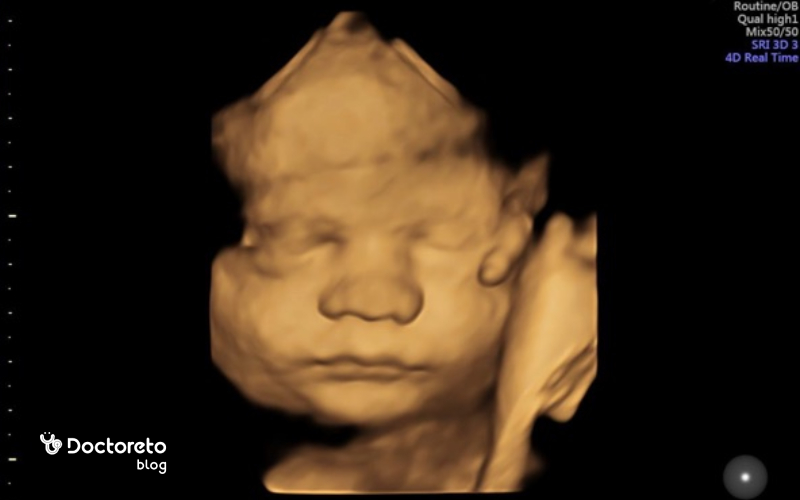

در هفته ۳۵ بارداری جنین حدود ۳۲ سانتیمتر میشود. اگر قد جنین را از سر تا پا اندازه بگیریم، تقریبا ۴۵ سانتیمتر است. وزن جنین در این هفته به ۲۵۰۰ گرم میرسد. از جمله تغییرات جنین در این هفته میتوان به موارد زیر اشاره کرد.

در هفته ۳۵ بارداری جنین چه شکلی است؟

در هفته سی و پنجم بارداری جنین تقریبا اندازه یک آناناس میشود. تمامی اندامها رشد کردهاند. کلیهها و کبد کار میکنند. وزن جنین در هفتههای آخر بارداری با سرعت بیشتری افزایش پیدا میکند. زیرا چربی درحالرشد زیر پوست و بین اندامها است.